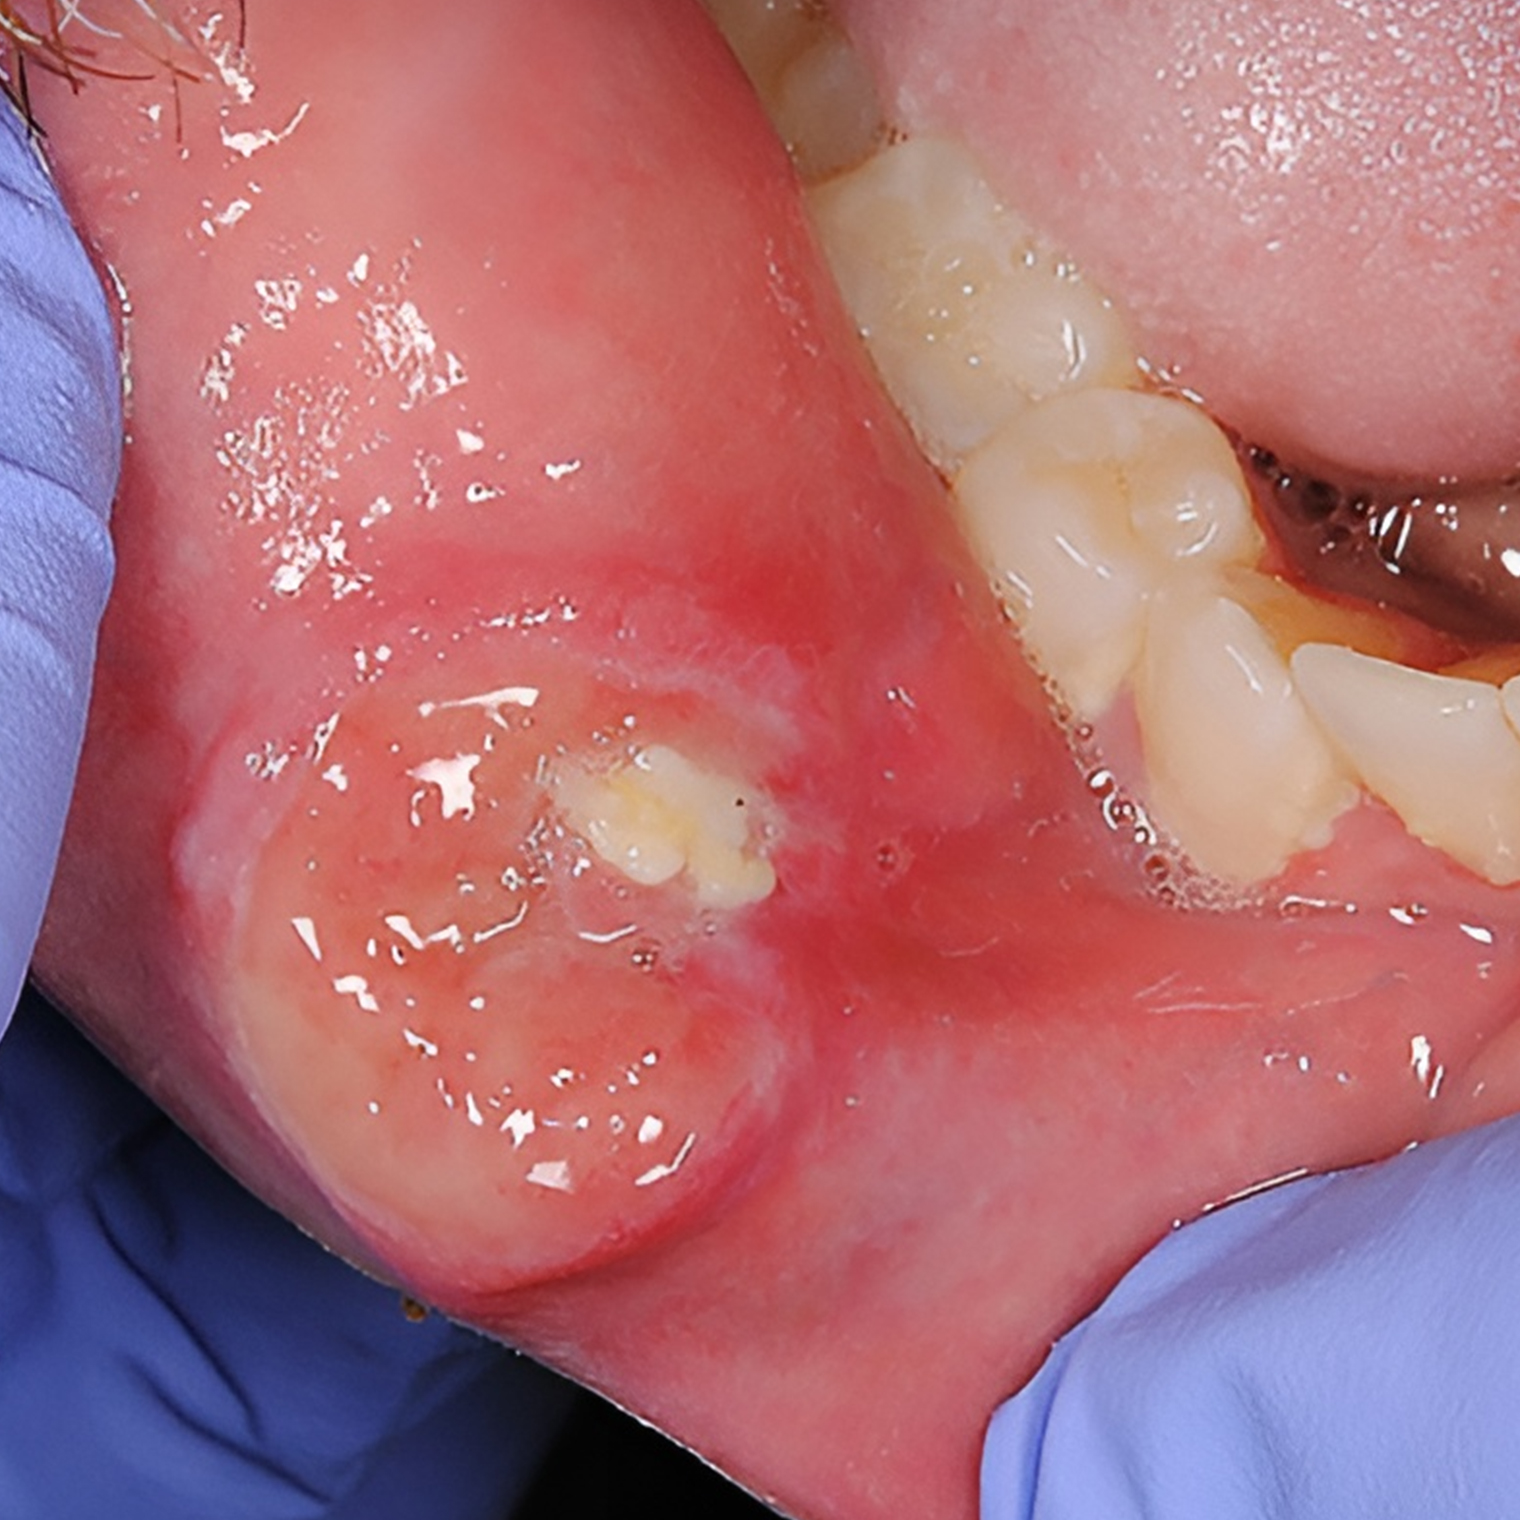

Первичный сифилис. В месте проникновения бактерии, обычно на половых органах, в прямой кишке или во рту, появляется шанкр — твердая, круглая и безболезненная язва. Поскольку она не доставляет неприятных ощущений, человек может ее не заметить.

Шанкр проходит в течение 3—6 недель. После заживления на его месте может остаться рубец.